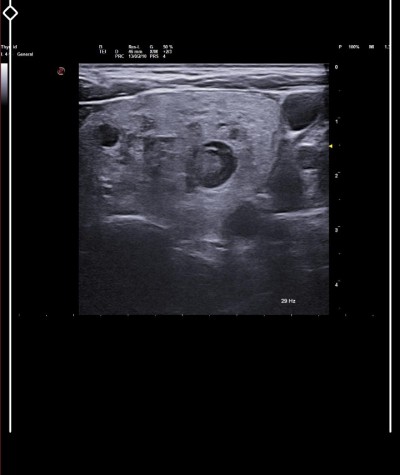

Senin nodüllerin var eyer 3-4 santimin üstüne çıktıysa alırlar zaten doktorlar

17×15 mm yaziyor yani 3..4 cm olmadan almicaklarmi

Buna doktor karar verir benim annemin ki vardı 2 cm di doktor biyopsi yaptı temiz gelince bunları alalım dedi annem istemedi istersen git doktor bakar ona göre alir